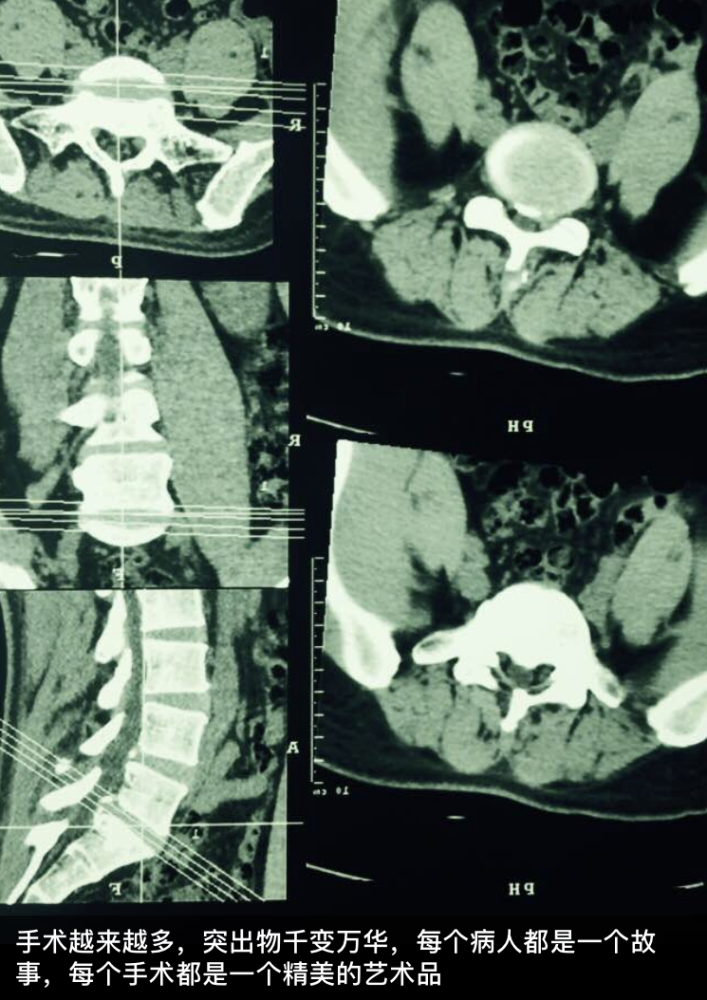

在占恭豪看来,手术越来越多,突出物千变万化,每个病人都是一个故事,每个手术都是一个精美的艺术品。唯有付诸全部心力,方能创造一个经典案例。